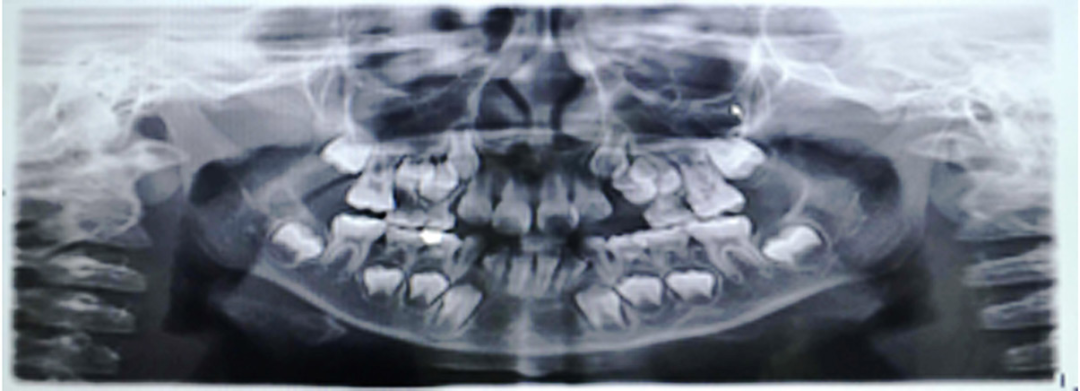

就像这个小朋友初诊检查头侧片子发现骨骼I类、牙齿III类咬合关系。但是,孩子家长拒绝接受治疗,觉得孩子换完牙就变好了,不会变成严重的地包天问题。

但是1年半之后,孩子前牙地包天问题加重,下颌前凸也很明显,这才又想要通过牙齿矫正改善孩子的牙齿咬合和面型情况。

早期阻断矫正地包天的牙齿、牙弓、颌骨的关系异常,抑制下颌的生长,促进上颌颌骨的生长,引导孩子颌面颌骨正常生长发育,建立良好的咬合关系和前牙的正常覆合覆盖,以及颌骨的矢状向关系和软组织面型,避免成年后做正颌外科手术,孩子也不受罪。